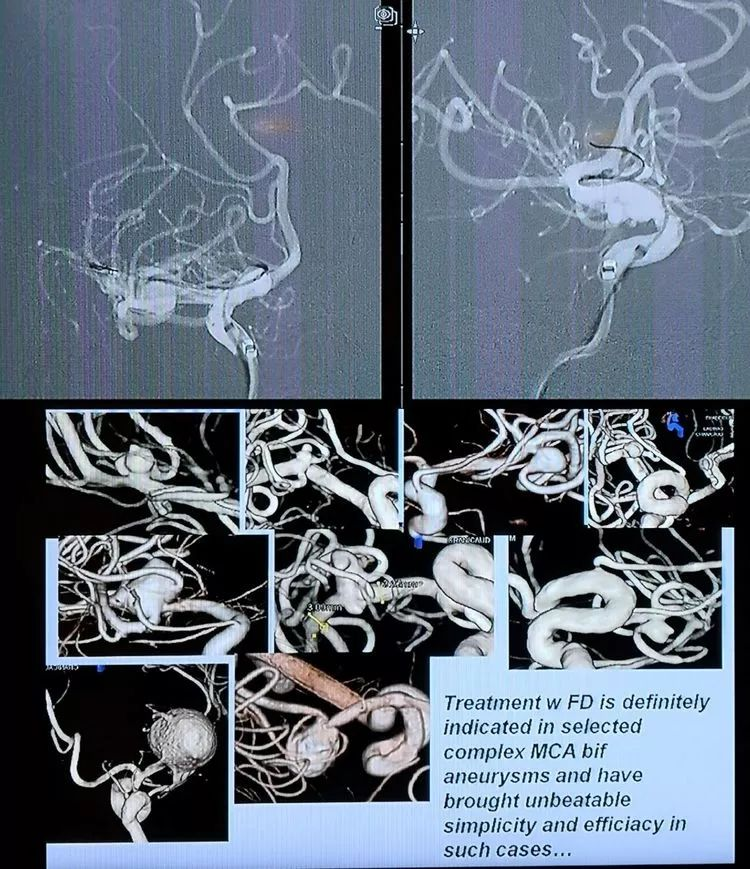

CASE 3 AN

-左侧大脑中动脉大型动脉瘤,上干累及,较为细小

-采用Pipeline shield,4毫米直径的具有磷脂涂层FD,动脉瘤区域稍外膨,支架网丝密度更大可能有利于愈合

-重点是血流导向重构治疗动脉瘤和保留上干

CASE 4 AN

-也是FD治疗,FRED Jr.血流重构

-采用最短的Fred jr,工作段在动脉瘤所在的细小分支,Jr近端无效工作段覆盖了较大分支

-又是FD ...不评论了

CASE 7 AN

- 对不起,还是FD...趋势啊

-一个下午6台动脉瘤,一个COIL都没有用,血流重构的重要性不言而喻